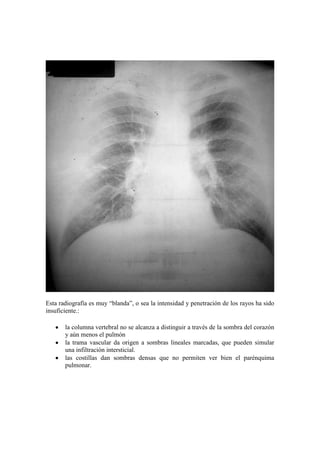

Esta radiografía es muy “blanda”, o sea la intensidad y penetración de los rayos ha sido

insuficiente.:

la columna vertebral no se alcanza a distinguir a través de la sombra del corazón

y aún menos el pulmón

la trama vascular da origen a sombras lineales marcadas, que pueden simular

una infiltración intersticial.

las costillas dan sombras densas que no permiten ver bien el parénquima

pulmonar.